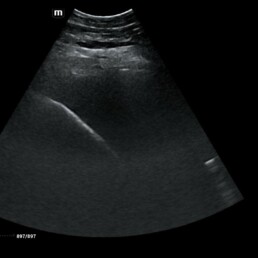

Weiterführende Untersuchungen

- Ultraschalluntersuchung der Leber aufgrund auffällig hoher Leberwerte im Blut

- möglicher Zusammenhang mit EMS/Übergewicht -> auch andere Ursachen bspw. Fettleber, Parasiten, Vergiftung denkbar

- Ultraschall lässt Verfettung der Leber vermuten